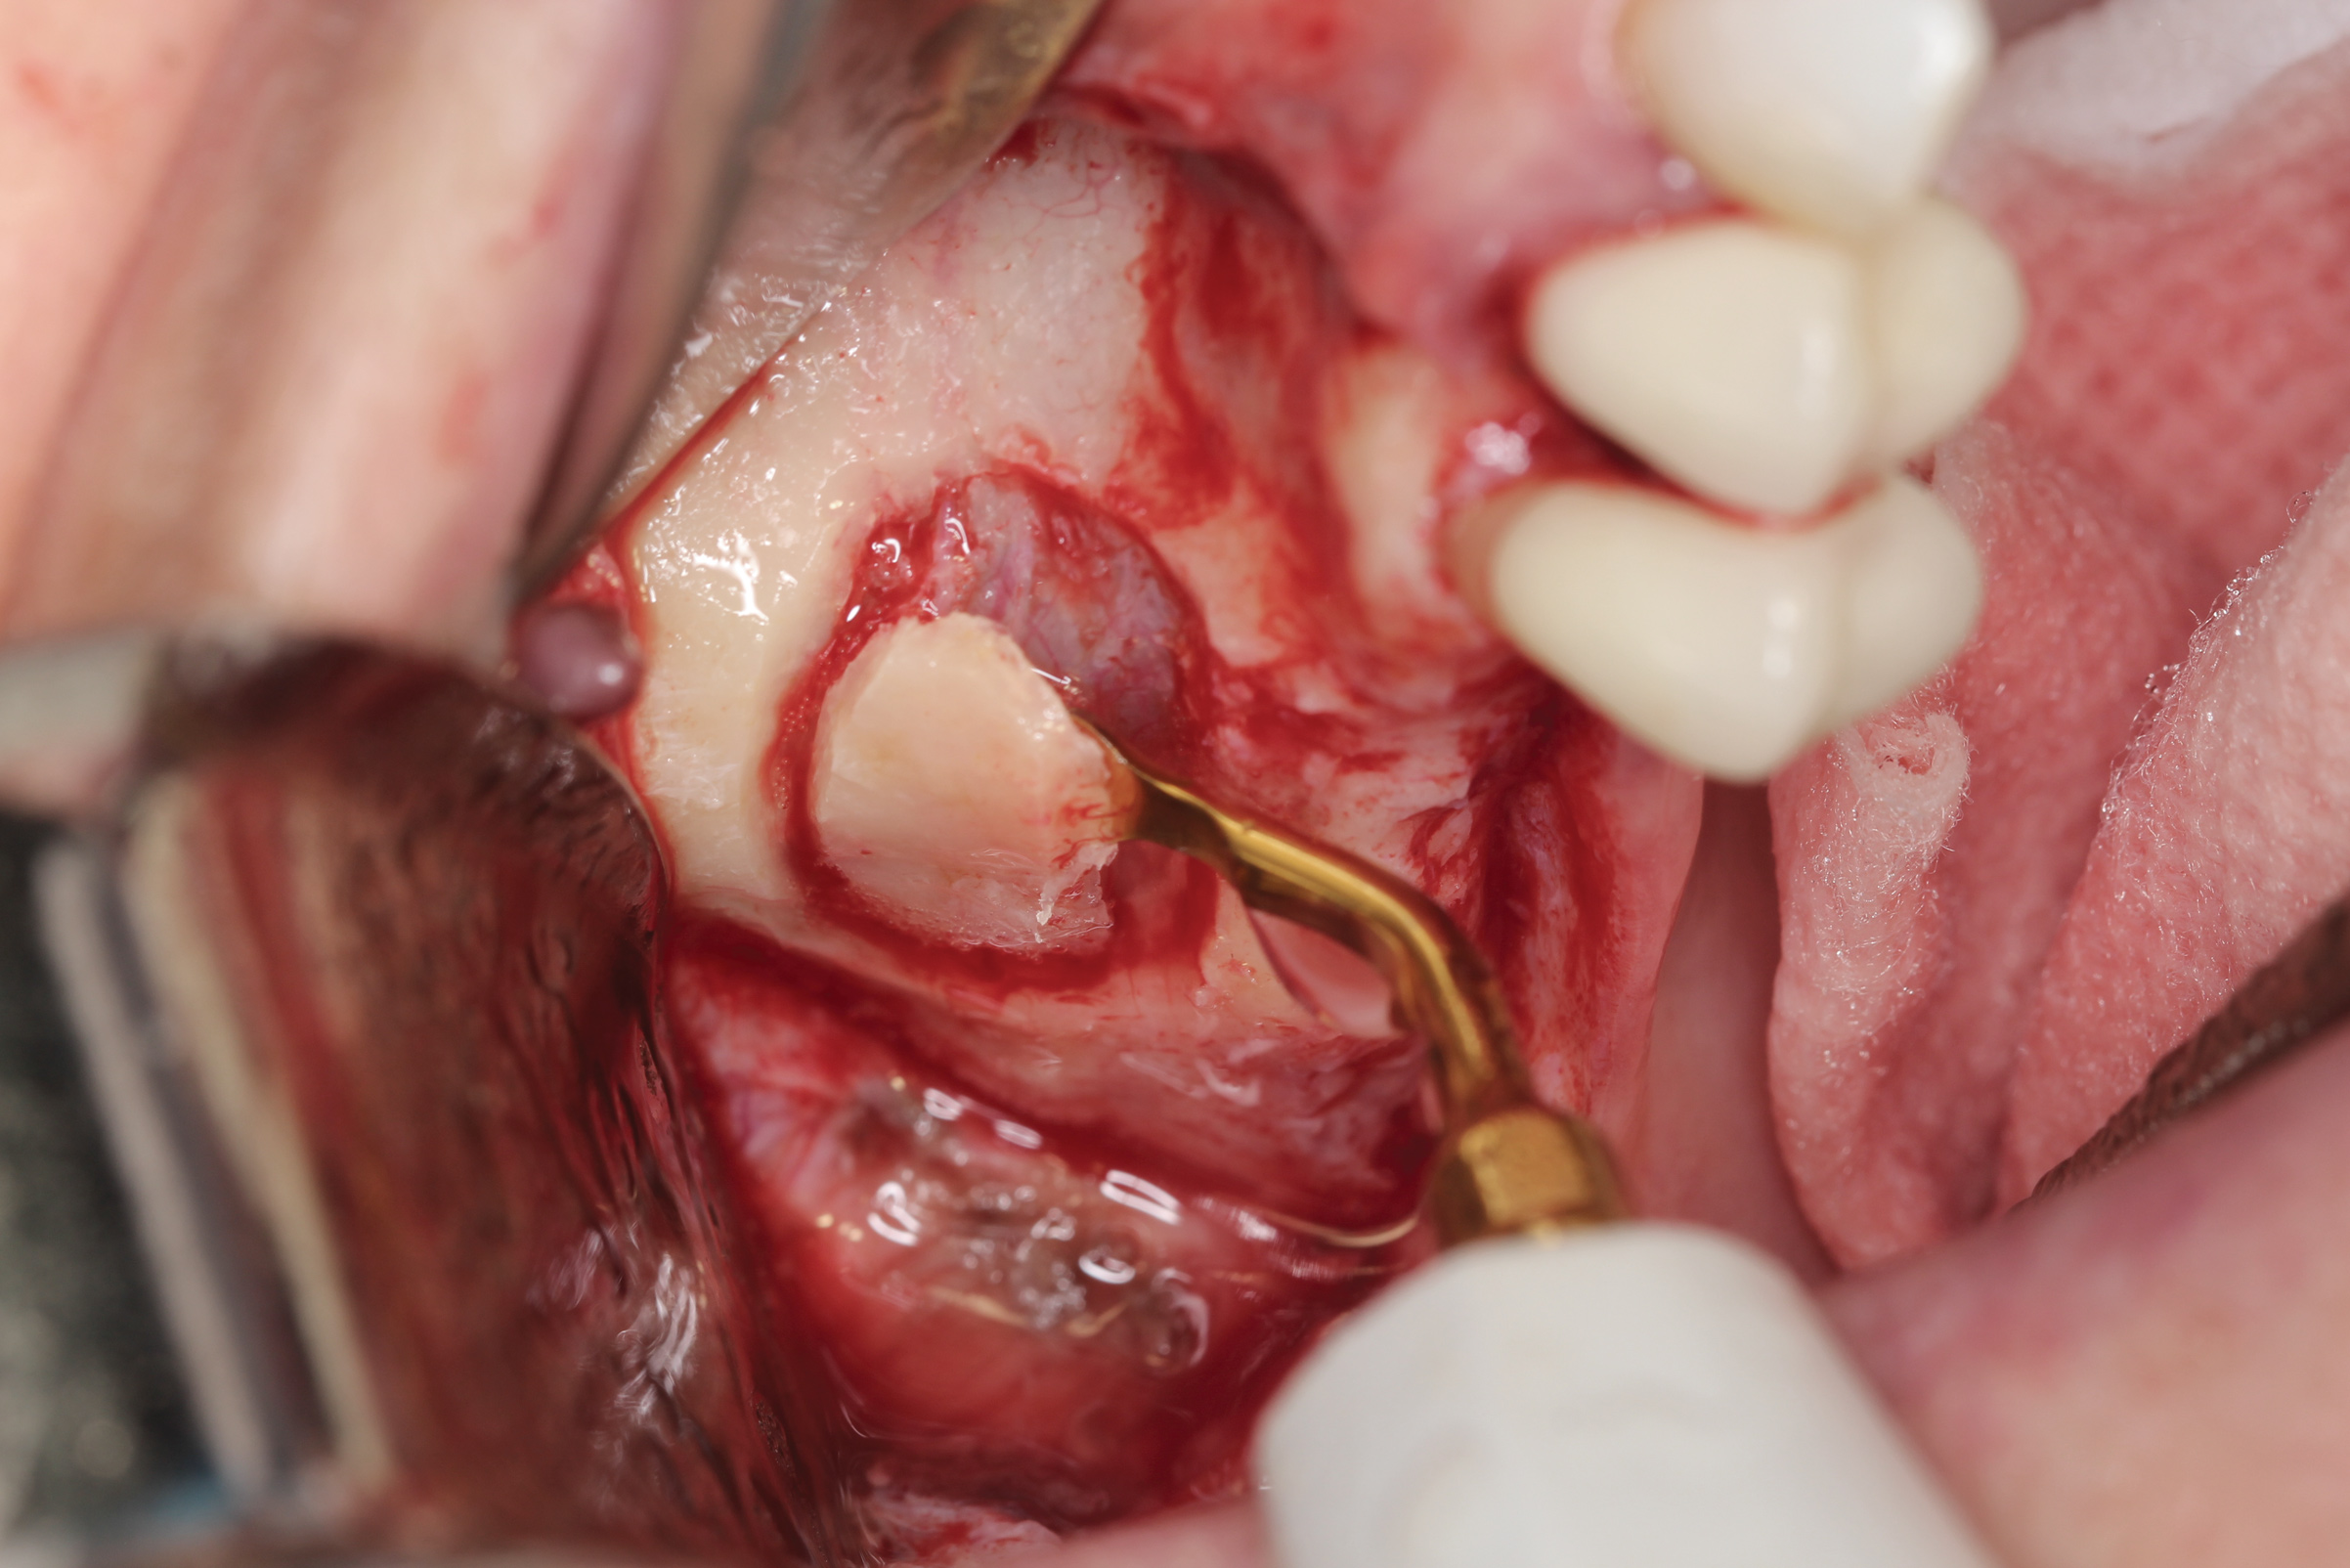

A 65-year-old male patient presented to the office with a fractured maxillary left lateral incisor (Figure 16). Radiographic analysis revealed minimal buccal bone. Having deemed the tooth nonrestorable, the clinician presented several options to the patient, which they carefully reviewed together. A socket-shield approach was selected with the goal of maintaining existing gingival zenith long-term.

Fig 16. Patient presented with fractured maxillary left lateral incisor. Radiographic analysis (not shown) revealed minimal buccal bone. A socket shield was planned during tooth extraction to preserve gingival contours.

Figure 16

Fig 17. The root was sectioned mesial-distal, followed by removal of the palatal root half.

Figure 17

Fig 18. Remaining facial root was contoured to a thickness of 1.5 mm.

Figure 18